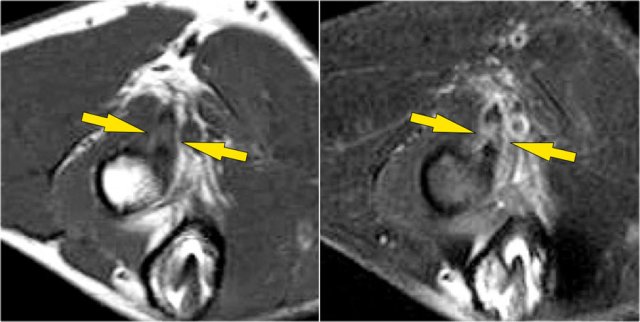

Here a different patient.

Notice that it is a young patient, because the physis is still open.

There is a large osteochondral lesion in the lateral trochlea (yellow arrows).

Notice the edema in the subchondral bone (red arrow).

The cartilage is still intact.